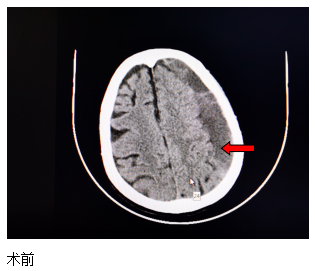

近日,一位84歲高齡患者來(lái)江寧中院就診,表現(xiàn)為:右側(cè)肢體的力量下降、不能獨(dú)立站立、言語(yǔ)不利、吐字不清。經(jīng)頭部CT檢查發(fā)現(xiàn),患者左側(cè)大面積慢性硬膜下血腫,嚴(yán)重壓迫腦組織。

患者收入院后,完善各項(xiàng)檢查,無(wú)明顯手術(shù)禁忌,中醫(yī)院神經(jīng)外科團(tuán)隊(duì)經(jīng)過精心周全的準(zhǔn)備,為其實(shí)施了腦膜中動(dòng)脈栓塞結(jié)合硬通道血腫穿刺引流的復(fù)合手術(shù)。術(shù)后第二天,患者肢體無(wú)力的癥狀得到了明顯改善,語(yǔ)言表達(dá)也恢復(fù)如初。患者及家屬對(duì)此治療效果非常滿意。